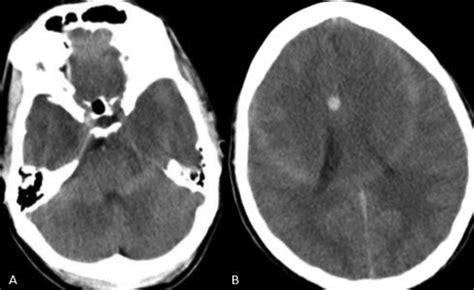

Web the white matter and the grey matter are special areas in the brain and the spinal cord. The term is most often used when trying to differentiate cytotoxic from vasogenic edema. Web the result is that the cerebral white matter is of higher attenuation than the cortical grey matter; This sign can be seen in diffuse hypoxic injury due to cerebral edema. Grey matter in the brain and spinal cord. In the brain, grey matter is present on the outer side and many grey matter nuclei are embedded in the white matter in the deeper area of the brain. The grey matter is made up of the cell bodies of neurons, some unmyelinated axons, and glial cells. The term is most often used when trying to differentiate cytotoxic from vasogenic edema. Web a lot of confusion revolves around the distinction between gray and white matter in the brain, but the difference is actually a pretty simple one. Created for people with ongoing healthcare needs but benefits everyone.

This sign can be seen in diffuse hypoxic injury due to cerebral edema. Web the white matter and the grey matter are special areas in the brain and the spinal cord. Hiep le answered nephrology and dialysis 43 years experience that means normal. Location of gray matter and white matter within the. Web a lot of confusion revolves around the distinction between gray and white matter in the brain, but the difference is actually a pretty simple one. 2 doctor answers • 2 doctors weighed in share dr. A pseudosubarachnoid hemorrhage sign is also present which demonstrates increased density within the basal cisterns. Grey matter in the brain and spinal cord. The term is most often used when trying to differentiate cytotoxic from vasogenic edema. The grey matter is made up of the cell bodies of neurons, some unmyelinated axons, and glial cells. Created for people with ongoing healthcare needs but benefits everyone.